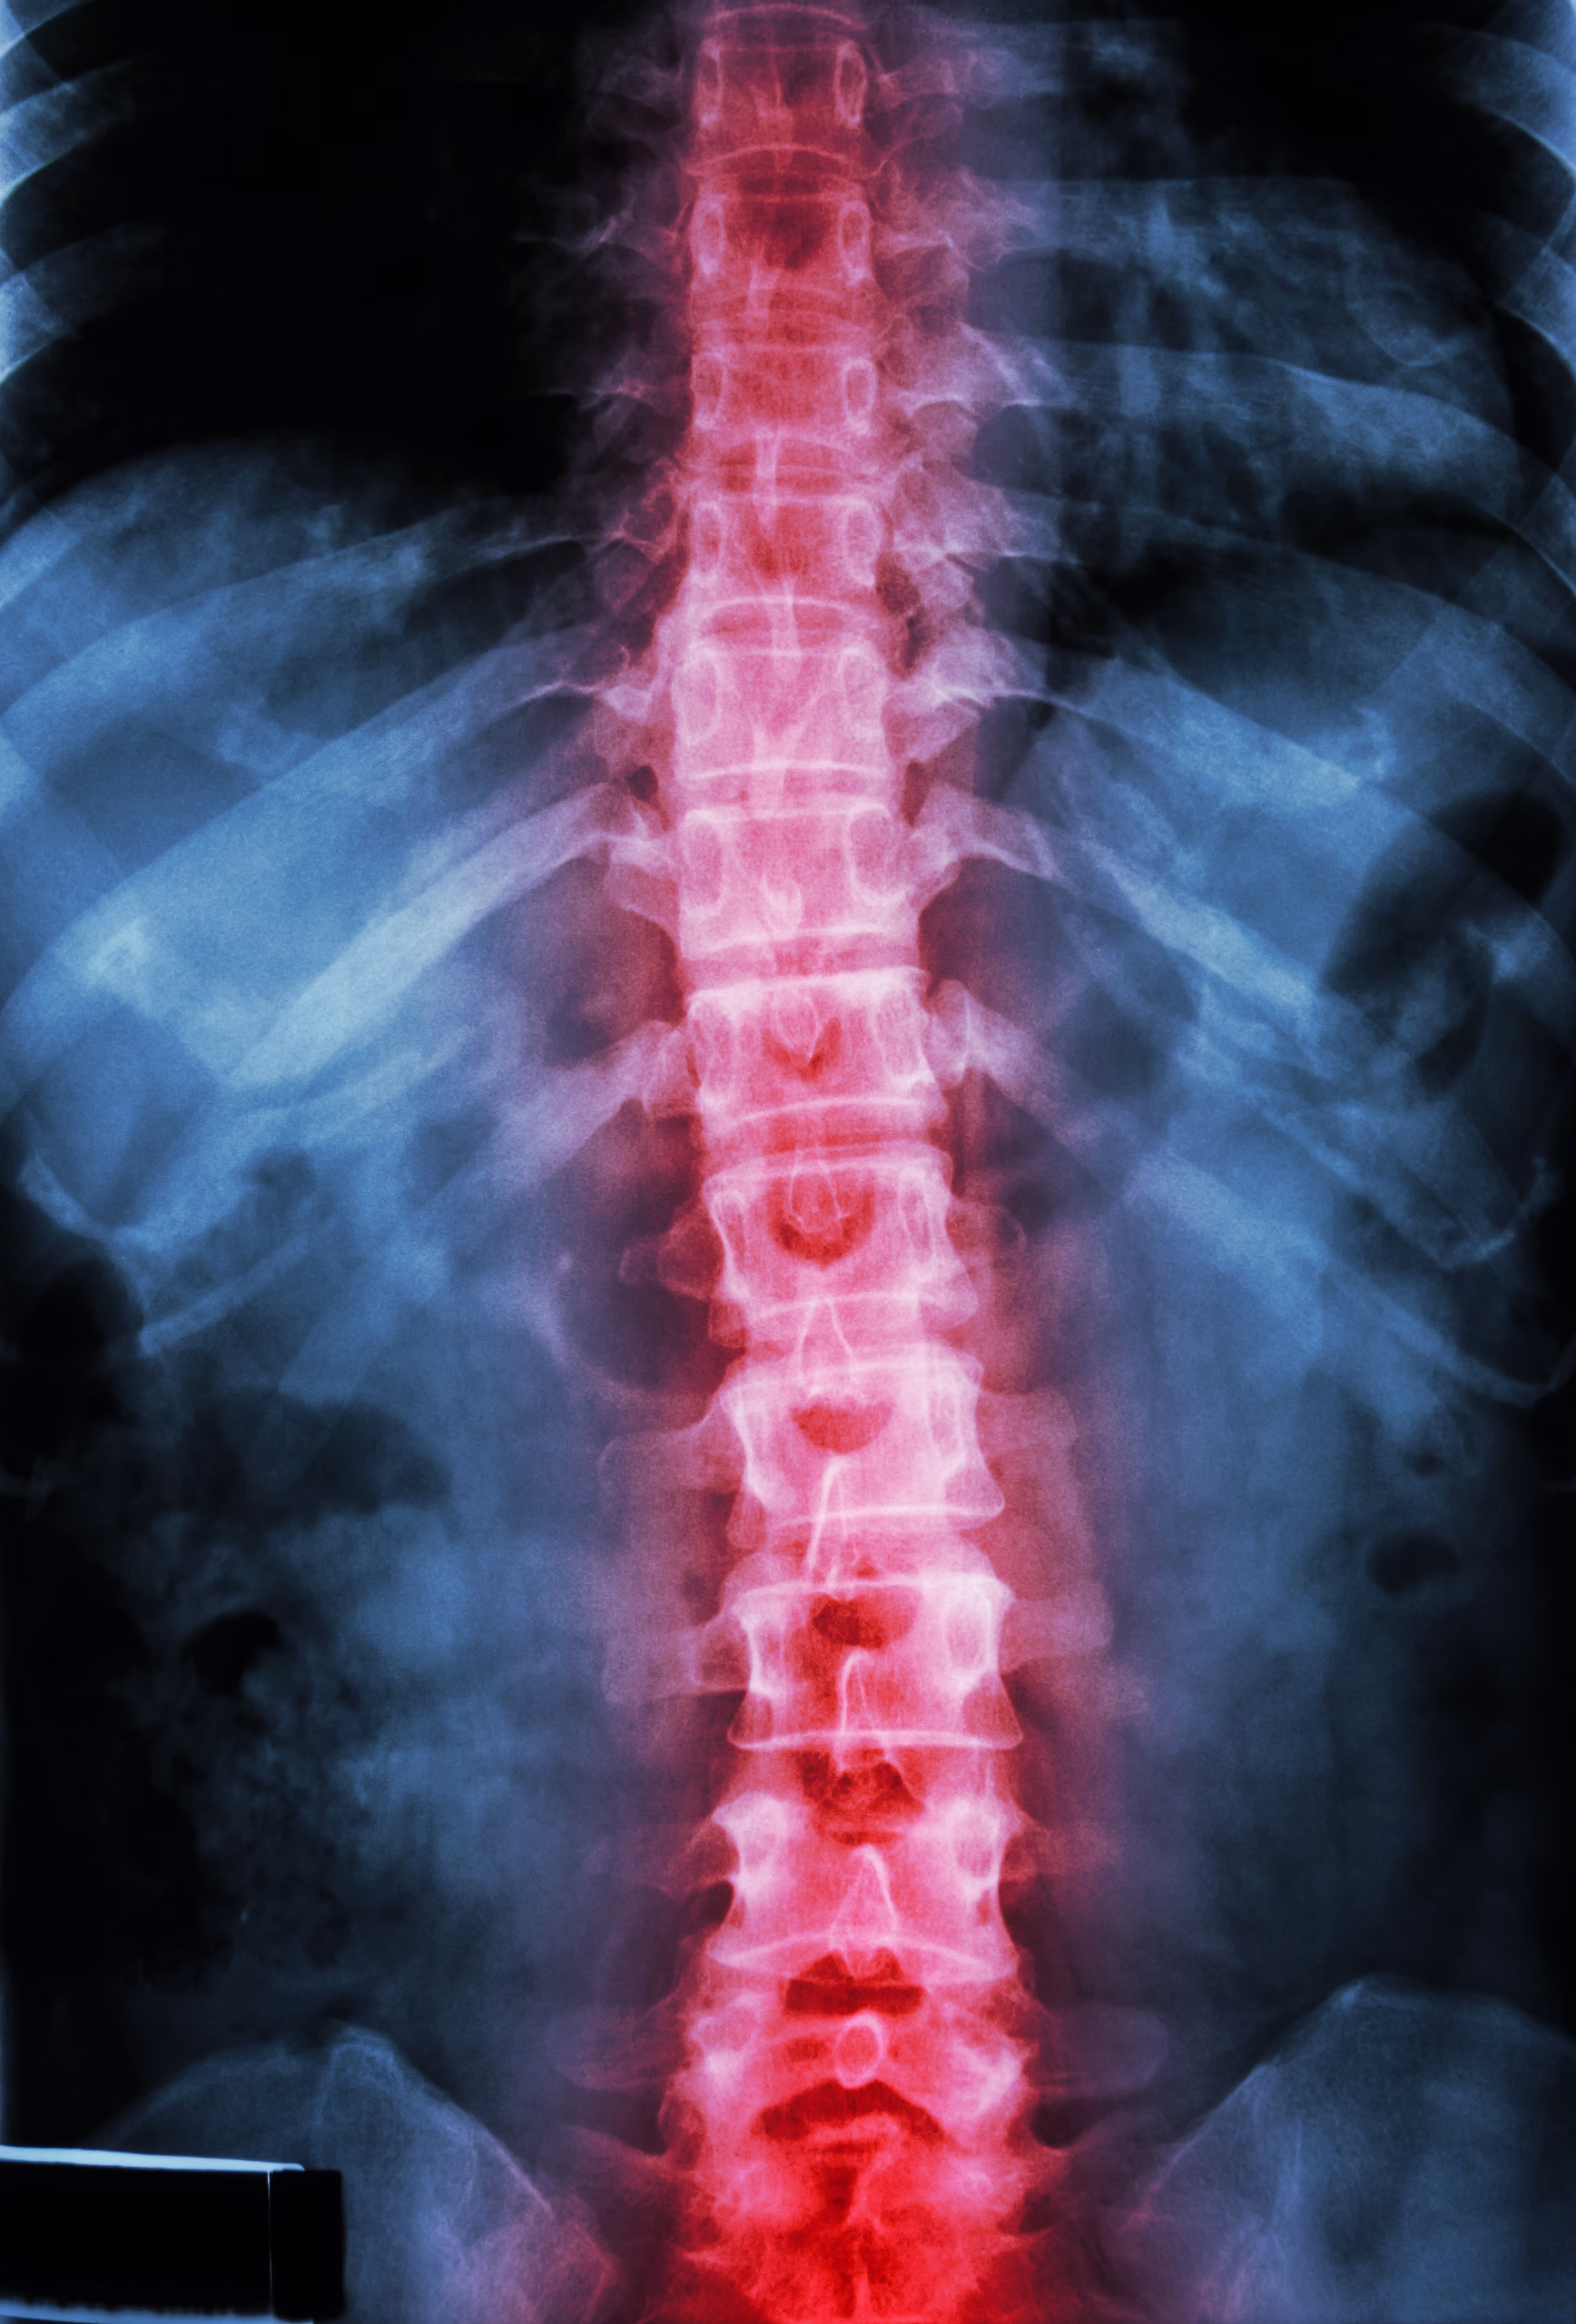

Les blessures à la tête, à la colonne vertébrale ou au bassin peuvent entraîner des conséquences sérieuses, voire permanentes. Un coup à la tête peut causer une commotion cérébrale, une hémorragie interne ou une fracture du crâne. Un traumatisme à la colonne vertébrale peut provoquer une compression médullaire et des troubles moteurs ou sensitifs.

Au niveau rachidien, une douleur intense au cou ou au dos, un engourdissement, une sensation de brûlure ou une perte de contrôle des membres indiquent une lésion possible de la moelle épinière.